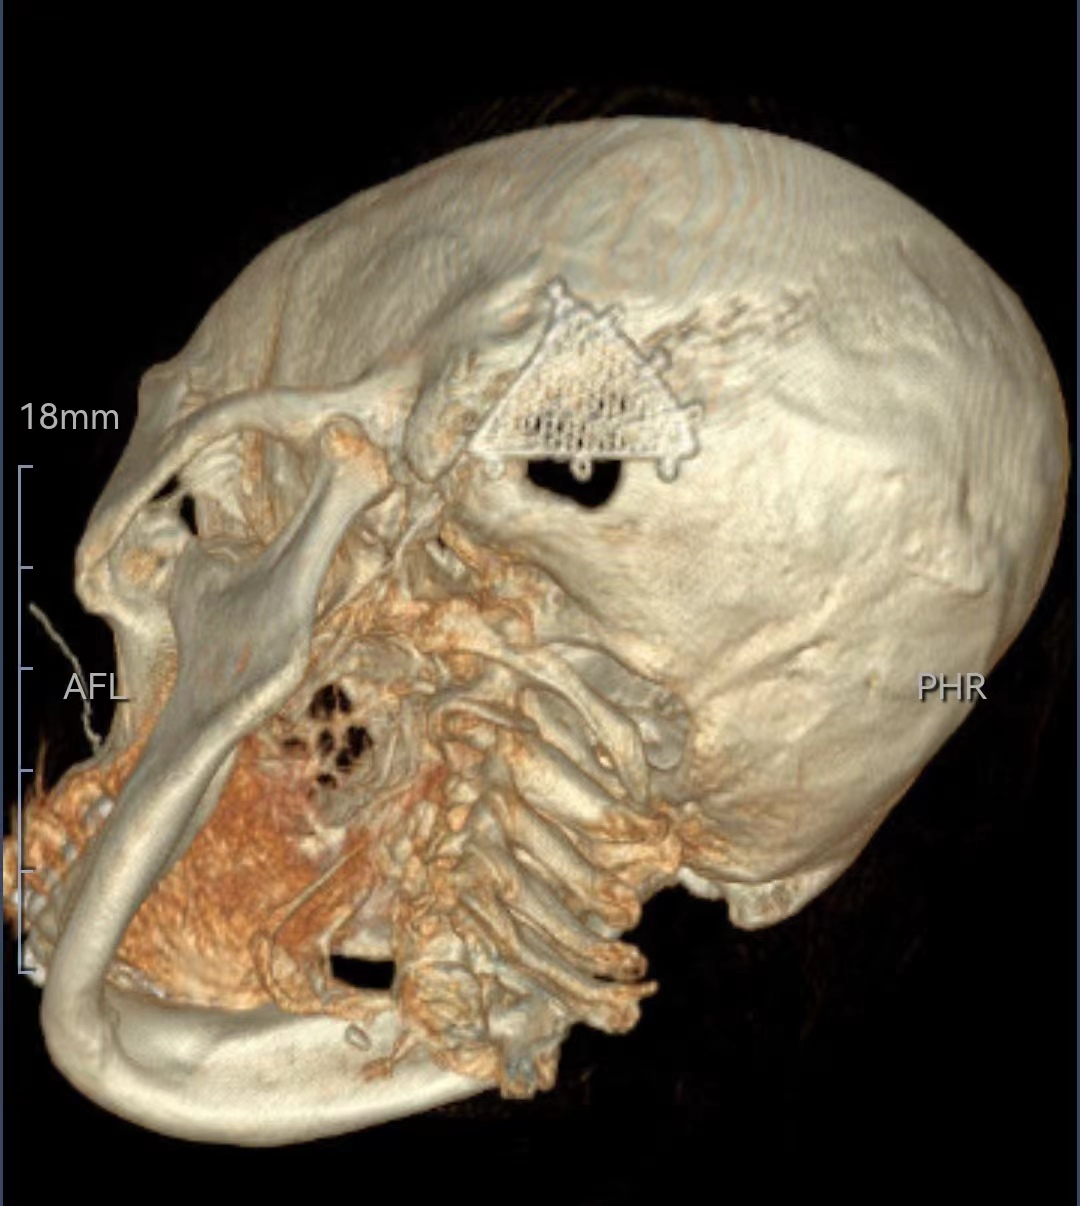

既往史:8年前在外院诊断为左侧舌咽神经痛,2016年外院行微血管减压术,术后疼痛缓解4年后复发。复发后做过射频消融术、局部阻滞,均无效。

诊断:左侧舌咽神经痛(术后复发)